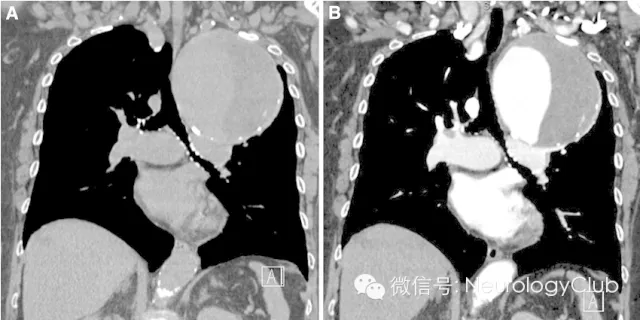

阴阳征表现为增强CT上,在扩张的卵圆形动脉截面内,可见半强化和半无强化区,形态酷似道教的阴阳符号。

阴阳征见于附壁血栓形成的真性和假性动脉瘤患者。动脉瘤为局限性或弥漫性的动脉管腔扩张,大于其正常直径的50%。假性动脉瘤指动脉管壁被撕裂或穿破,血液自此破口流出而被主动脉邻近的组织包裹而形成血肿,多由创伤所致。大动脉瘤和假性动脉瘤容易形成附壁血栓,因此血流仅充盈部分管腔。阴阳征中,造影剂充盈增强的部分代表通畅的管腔,而无造影剂充盈的部分则代表附壁血栓的形成。

病例4:右锁骨下动脉动脉瘤